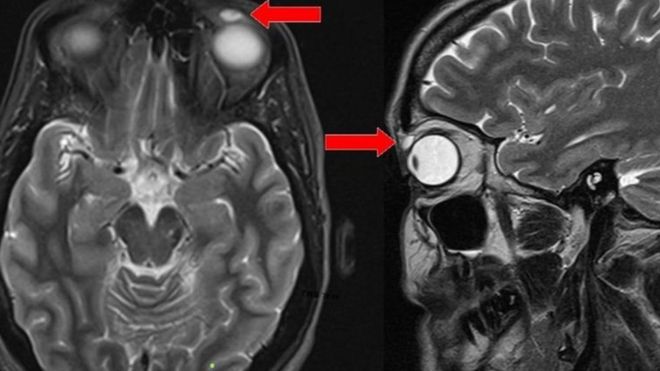

Una resonancia magnética mostró el quiste sobre el ojo de la mujer.

Los investigadores del hospital de Ninewell le realizaron una resonancia magnética, después de que el médico de cabecera de la paciente la remitiera al departamento de Oftalmología.

Las imágenes de la resonancia revelaron un quiste con forma ovoide de unos 8mm de longitud, pero no había evidencia de que hubiese algo dentro.